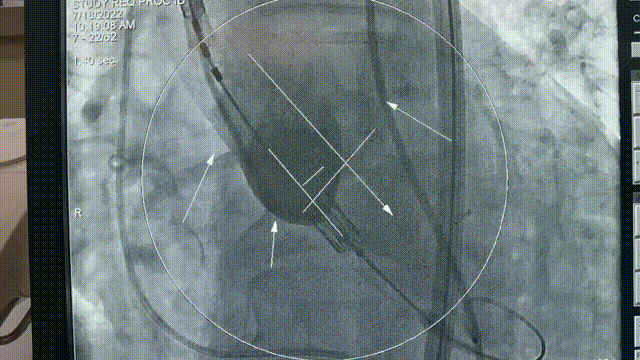

术前超声1